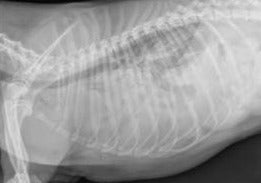

Le but de cette conférence est de faire le point sur tous les types de plaies pénétrantes du thorax: empalement par un objet contondant, épillet induisant un pneumothorax, volet costal suite à une morsure. L’interêt du scanner sera déterminant dans l’approche chirurgicale. Les cas d’épillet se gérant le plus souvent sous thoracoscopie.